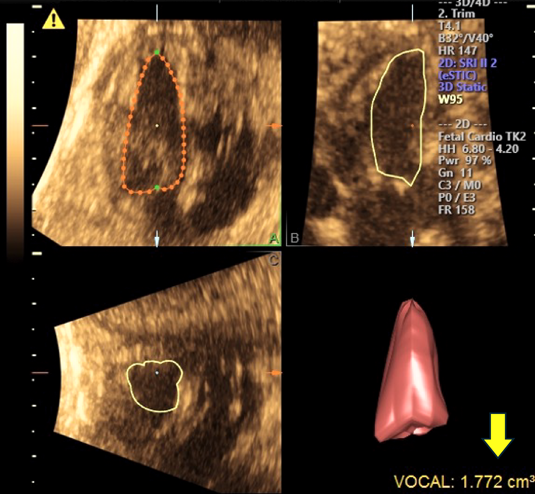

6.2 STIC法による4D画像を用いたEFの計測

通常,高画質でフレームレートが高い4Dエコー画像を取得するためには,複数の心拍の画像を組み合わせるために心電図同期が必要であるが,胎児は心電図を取得することができない.STIC法は心電図同期を必要とせず,画像上の心臓の周期的な変化を読み取ることにより胎児の心拍数・心周期を検出し,心臓全体をスキャンして取り込んだ画像データを,胎児の心周期に合わせてそれぞれ3D画像として合成して1心拍分の心臓全体の動画像を構築する4D超音波技術である.画像の取得には専用の超音波診断装置とプローブを必要とする.

STIC法を用いて取得した4D画像データを,Virtual Organ Computer-aided AnaLysis(VOCAL)を用いて解析することで心室容積を算出することができる(Fig. 8).この方法を用いて計測した正常胎児の在胎週数と推定体重による心室容積の標準曲線が報告されている20).EFは在胎週数によらず一定とされ,左室,右室のEFの平均値はそれぞれ45%,46%と報告されている.

Pediatric Cardiology and Cardiac Surgery 41(1): 11-19 (2025)

Fig. 8 Spatio-Temporal Imaging Correlation (STIC)法によって取得した3DデータをVirtual Organ Computer-aided AnaLysis (VOCAL)を用いて解析して心室容積を算出した計測結果画面

矢印が容積の計測結果.